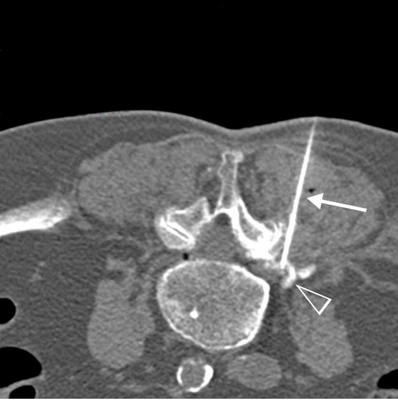

Dieser Eingriff ist so wenig invasiv und so komplikationsarm, dass er ambulant durchgeführt werden kann. In örtlicher Betäubung wird hierbei CT-gesteuert eine feine Nadel an die betroffene Nervenwurzel platziert und schmerzlindernde und entzündungshemmende Medikamente appliziert.

CT-gestützte Schmerztherapie: unmittelbar an die betroffene Nervenwurzel wird eine feine Nadel millimetergenau platziert (Pfeil), durch Beimischung von Röntgen-Kontrastmittel kann die Verteilung der applizierten Medikamente sichtbar gemacht werden (Pfeilspitze).